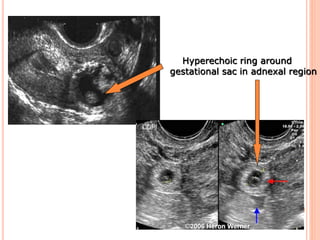

1.‘Bagel’ sign – Hyperechoic ring around gestational sac in

adnexal region

Hyperechoic ring around

gestational sac in adnexal region

Ring sign — a hyperechoic ring around an

extrauterine gestational sac.